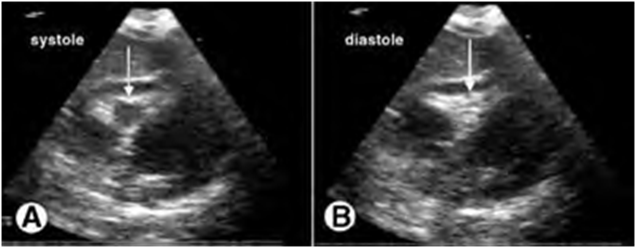

RV early diastolic collapse